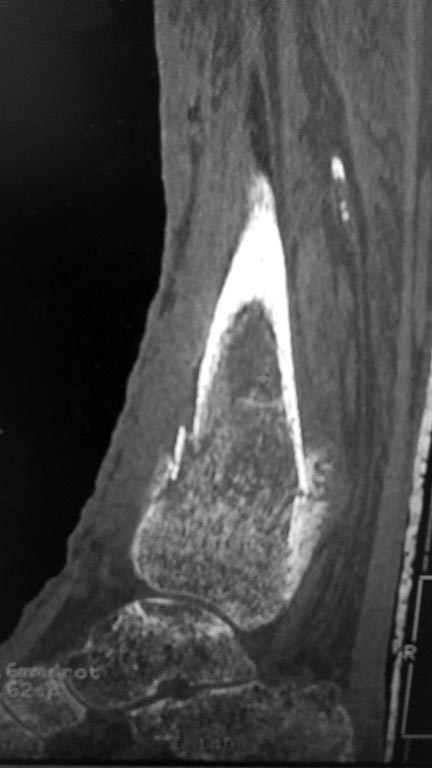

Перелом костей голени в нижней трети

Добрый день! Обратилась женщина 1958 г.р. Травма 08.09.16. Почувствовала боль в правой голени во время сна.

Лечилась амбулаторно с Ds: закрытый перелом костей правой голени в нижней трети без смещения. Повторную травму исключает. На контрольных Rg выявлено смещение отломков, признаки консолидации.

в анамнезе сахарный диабет I типа в течении 29 лет. лабильное течение. Диабетическая нефропатия. ХБП V ст. ХПН терминальная стадия. Хронический програмный гемодиализ. Ренальная остеодистрофия. Принимает лантус 6 Ед *1 раз в сутки. уровень сахара крови 12-15 ммоль\литр. Креатинин 543 мкмоль\литр, ЩФ 1270 Е\л.

Больная настроена на оперативное лечение. Какой вариант лечения предпочтителен на ваш взгляд?